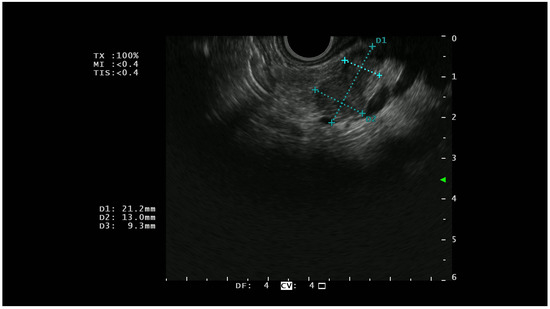

On EUS, basal analysis PTENs typically appear as homogeneous hypoechoic lesions with regular margins (Figure 1); sometimes they can have a cystic appearance [22] while in the most advanced cases, they can lose these characteristics, acquiring features more similar to pancreatic adenocarcinoma [23].

Figure 1.

A hypoechoic lesion of 21 mm with regular margins (identified by the blu +) and an ipoechoic appearance; at histopathological analysis the lesion was a G1 NET.